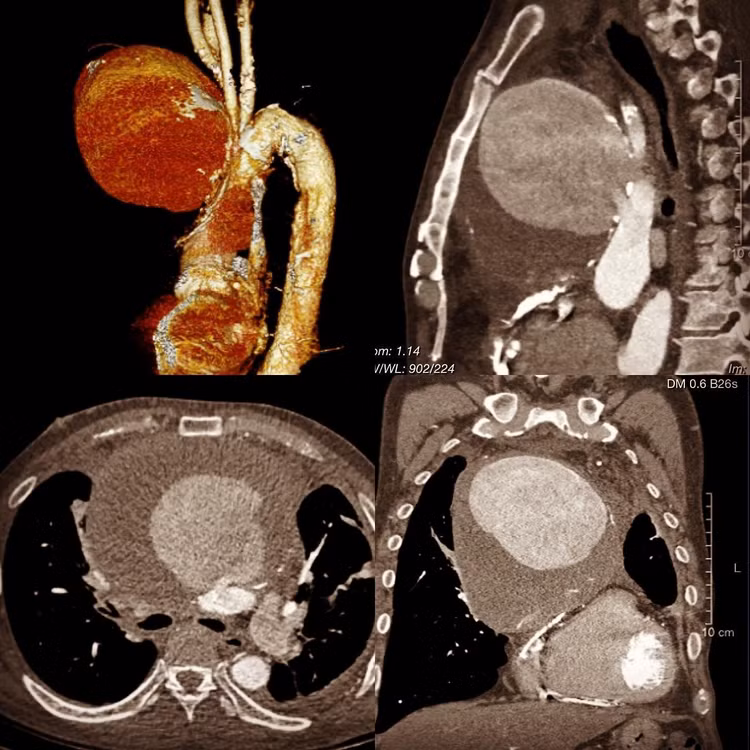

Kết quả chụp CT có tiêm thuốc cản quang: Trung thất trước trên có khối giả phình mạch khổng lồ kích thước 100x127x123mm. Khối phình chèn ép làm hẹp động mạch phổi phải đoạn nằm giữa động mạch chủ lên và cột sống (đường kính chỗ hẹp ~7mm), chèn ép tĩnh mạch cửa trên sang phải và ra sau. Tĩnh mạch vô danh bị chèn ép ra sau.

Bệnh nhân được kết luận: Khối giả phình động mạch chủ ngực khổng lồ và được phẫu thuật dẫn lưu ổ giả phình. Sau mổ, diễn biến tốt.

phinh-dong-mach-chu-nguc-khong-lo.jpg